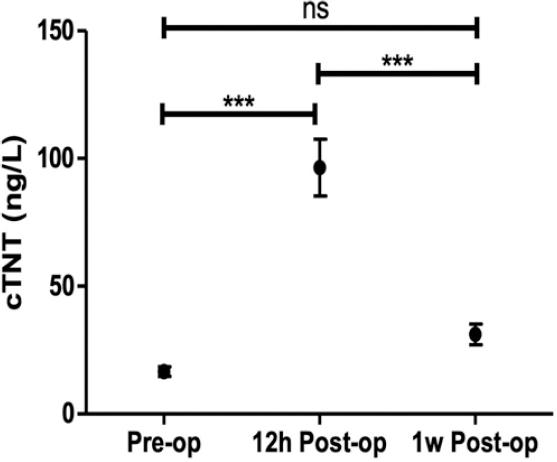

Figure 3 shows the changes of troponin T levels in patients undergoing LBBAP before operation, 12 h after operation, and 1 week after operation, with statistical differences. Compared with those before the operation, the levels of troponin T increased significantly at 12 h after operation (96.45 ± 11.07 [69.06] vs. 16.59 ± 1.84 [11.92] ng/L, p < 0.001). The levels of troponin T were significantly decreased at 1 week after operation compared with 12 h after operation (31.16 ± 4.04 [19.73] vs. 96.45 ± 11.07 [69.06] ng/L, p < 0.001), and there were no significant differences compared with levels before the operation.

Figure 3 Changes of troponin T levels. Troponin T pre-operative, 12 h post-operative, and 1 week post-operative levels in patients undergoing LBBAP were compared. Pre-op, pre-operative; 12 h post-op, 12 h post-operative; 1 w post-op, 1 week post-operative; cTNT, cardiac troponin T; ns, not significant; ***, p < 0.001.